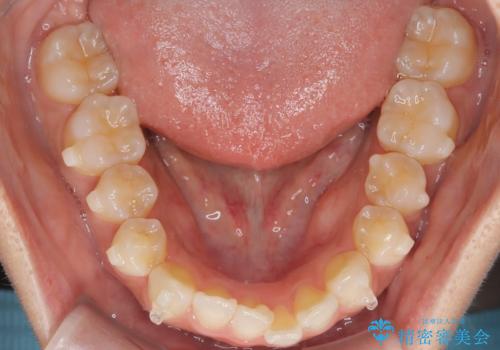

前歯の叢生を非抜歯で改善|インビザライン+IPR・遠心移動・FIX保定

- 前歯部のガタガタ(叢生)を非抜歯で改善するため、インビザラインによるマウスピース矯正を計画しました。抜歯は行わず、歯間をわずかに削るIPR(ディスキング)と奥歯を後方に移動させる遠心移動を併用して、歯を並べるスペースを確保します。歯列が整った後は、FIXリテーナー(固定式保定装置)で後戻りを防止し、安定した歯並びを維持します。

歯を抜きたくないというご希望に応え、インビザラインを用いて非抜歯で歯列を整えました。前歯に必要なスペースを確保するため、歯間をわずかに削るIPRと奥歯を後方に移動する遠心移動を組み合わせました。これにより自然で美しい歯並びを実現。治療終了後は、歯の裏側に目立たないFIXリテーナーを装着し、歯列の後戻りを効果的に防ぎました。患者様は治療中も審美的にストレスなく過ごされ、満足度の高い結果を得られました。